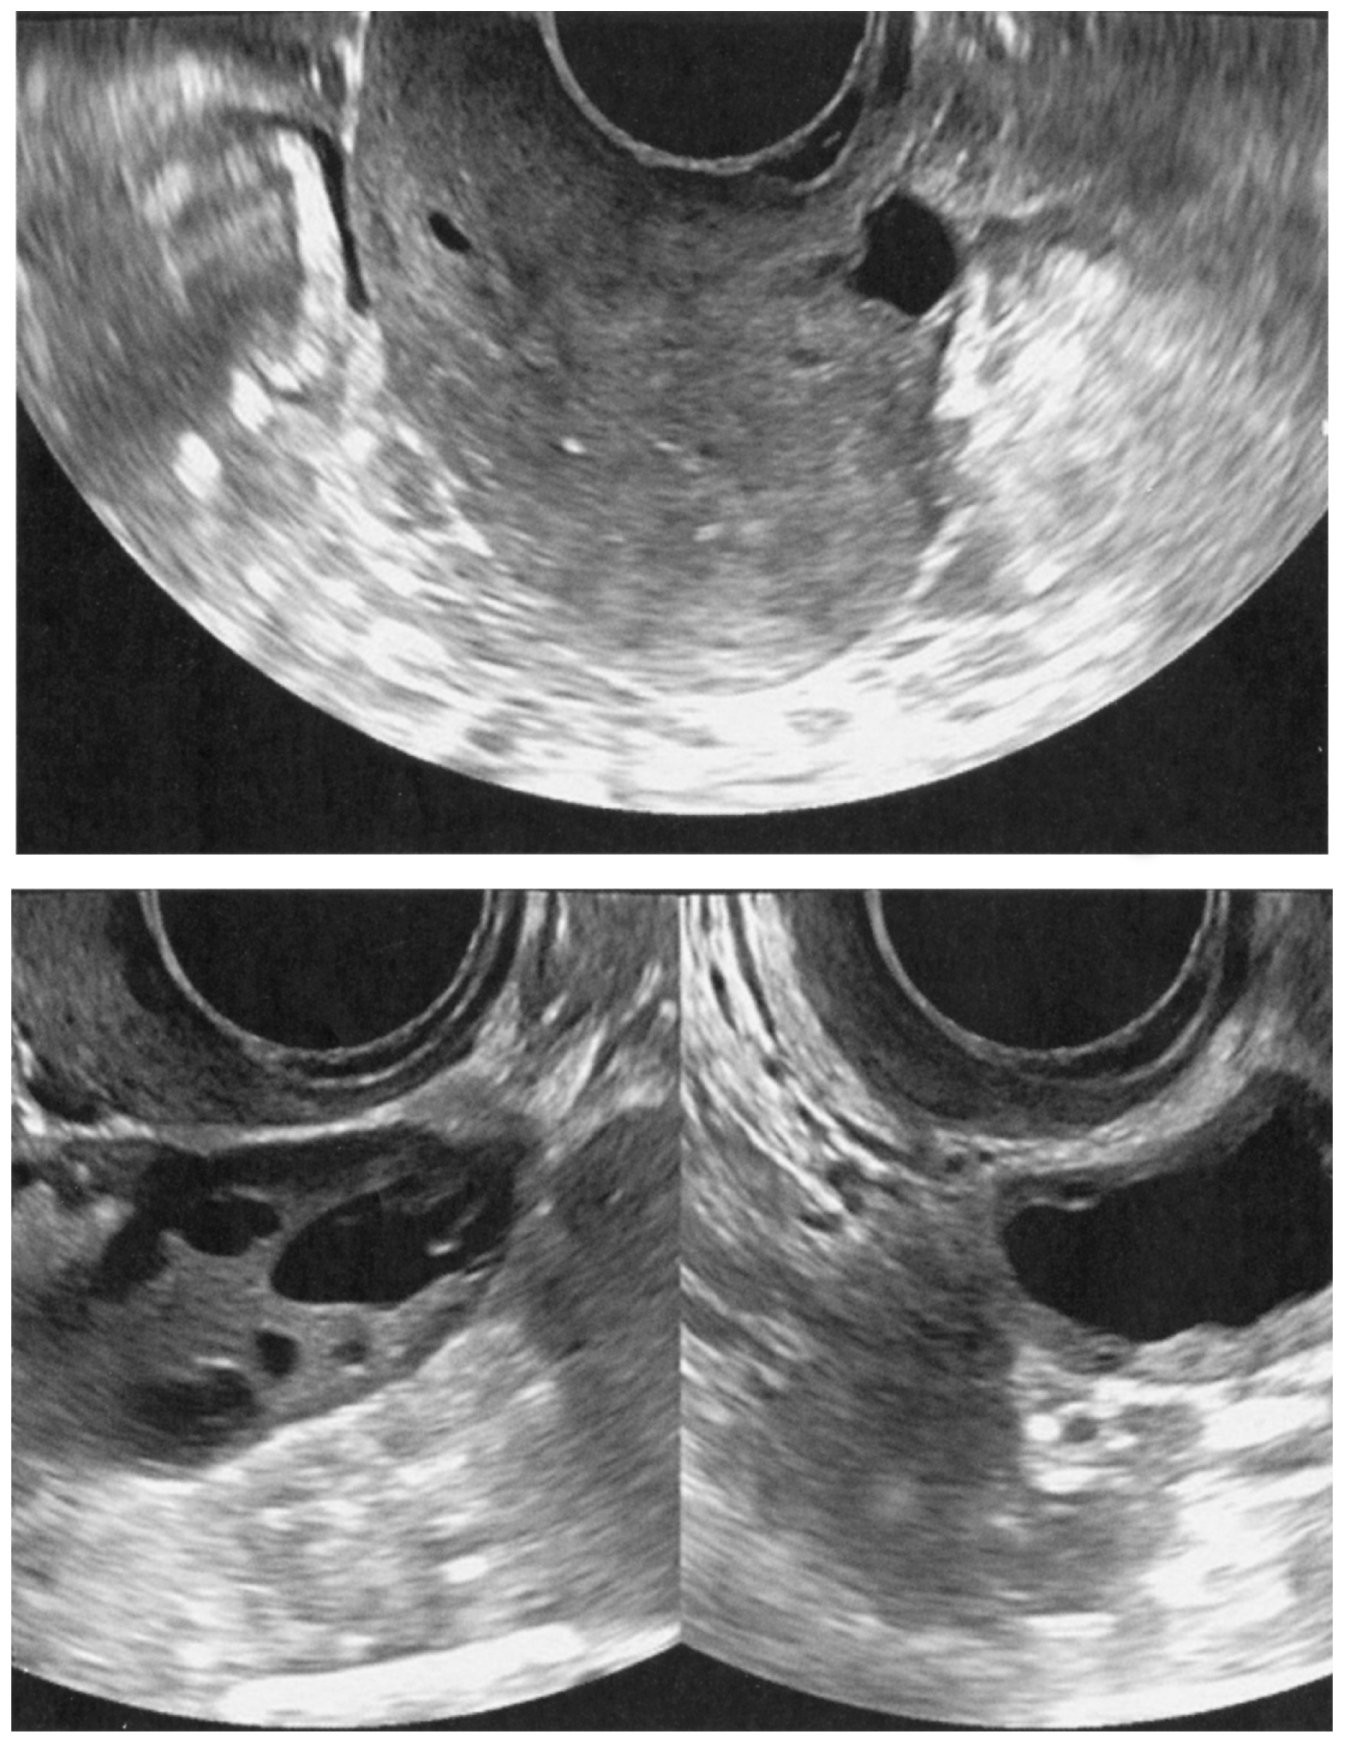

32歳の女性(1妊0産)。月経量の減少を主訴に来院した。6か月前から月経量と持続日数が減少している。月経周期は28日型,整,持続1日間。8か月前に妊娠10週で流産手術を受けたが,手術後しばらく腹痛と発熱が持続し,保存的治療で軽快した。流産以前の月経持続日数は6日間であった。身長158cm,体重62kg。体温36.2℃。脈拍72/分,整。血圧120/76mmHg。内診で子宮は正常大で,両側付属器は触知しない。血液所見:赤血球440万,Hb 12.2g/dL,Ht 44%,白血球6,600,血小板20万。血液生化学所見(月経7日目):LH 6.2 mIU/mL(基準1.8~7.6),FSH 7.8 mIU/mL(基準5.2~14.4),プロラクチン〈PRL〉6.6 ng/mL(基準15以下),エストラジオール120pg/mL(基準11~230),テストステロン42ng/dL(基準30~90)。経腟超音波像を下に示す。